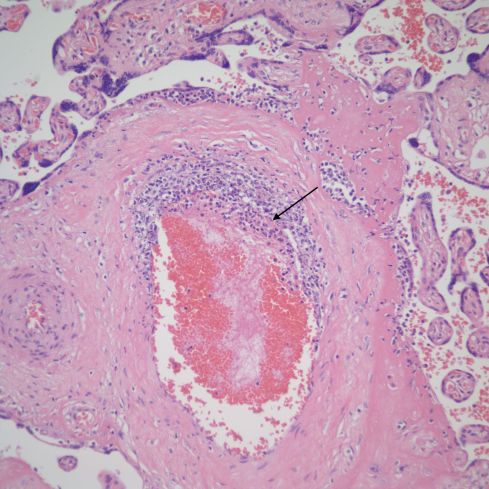

Another distinctive histologic feature in some cases VUE is that the lesion is confined to or predominant in the basal villi, referred to as basal villitis. These basal villi at the point of contact do not have an intervening syncytiotrophoblast layer (Fig 33-36).

Fig 33) This low magnification demonstrates an anchoring villus that is directly embedded (*) in the maternal floor cytotrophoblast layer (MF). The small branches near the point of contact show VUE in continuity with inflammation at the point of contact (arrows). The area in the rectangle is enlarged in the next figure. (H&E, 4x)

Fig 34) The villous stroma (V S) is directly embedded in the maternal floor (M F). The edges of the villi show loss of syncytiotrophoblast, fibrin, and lymphocytic infiltration. (H&E, 20x)

Fig 35) The basal villus (B V) demonstrates a loss of the fibrinoid layer (between the arrows) and some disruption of the cytotrophoblastic shell at the point of contact. There is a concentration of lymphocytes in the decidua beneath the contact and in continuity with the inflammation in villus. (H&E, 10x)

Fig 36) A higher magnification of the prior figure showing more clearly the lymphocytes appearing to percolate through the cytotrophoblastic shell of the maternal floor. The arrow demonstrates a small thrombus in a the anchoring villus vessel. (H&E, 20x)